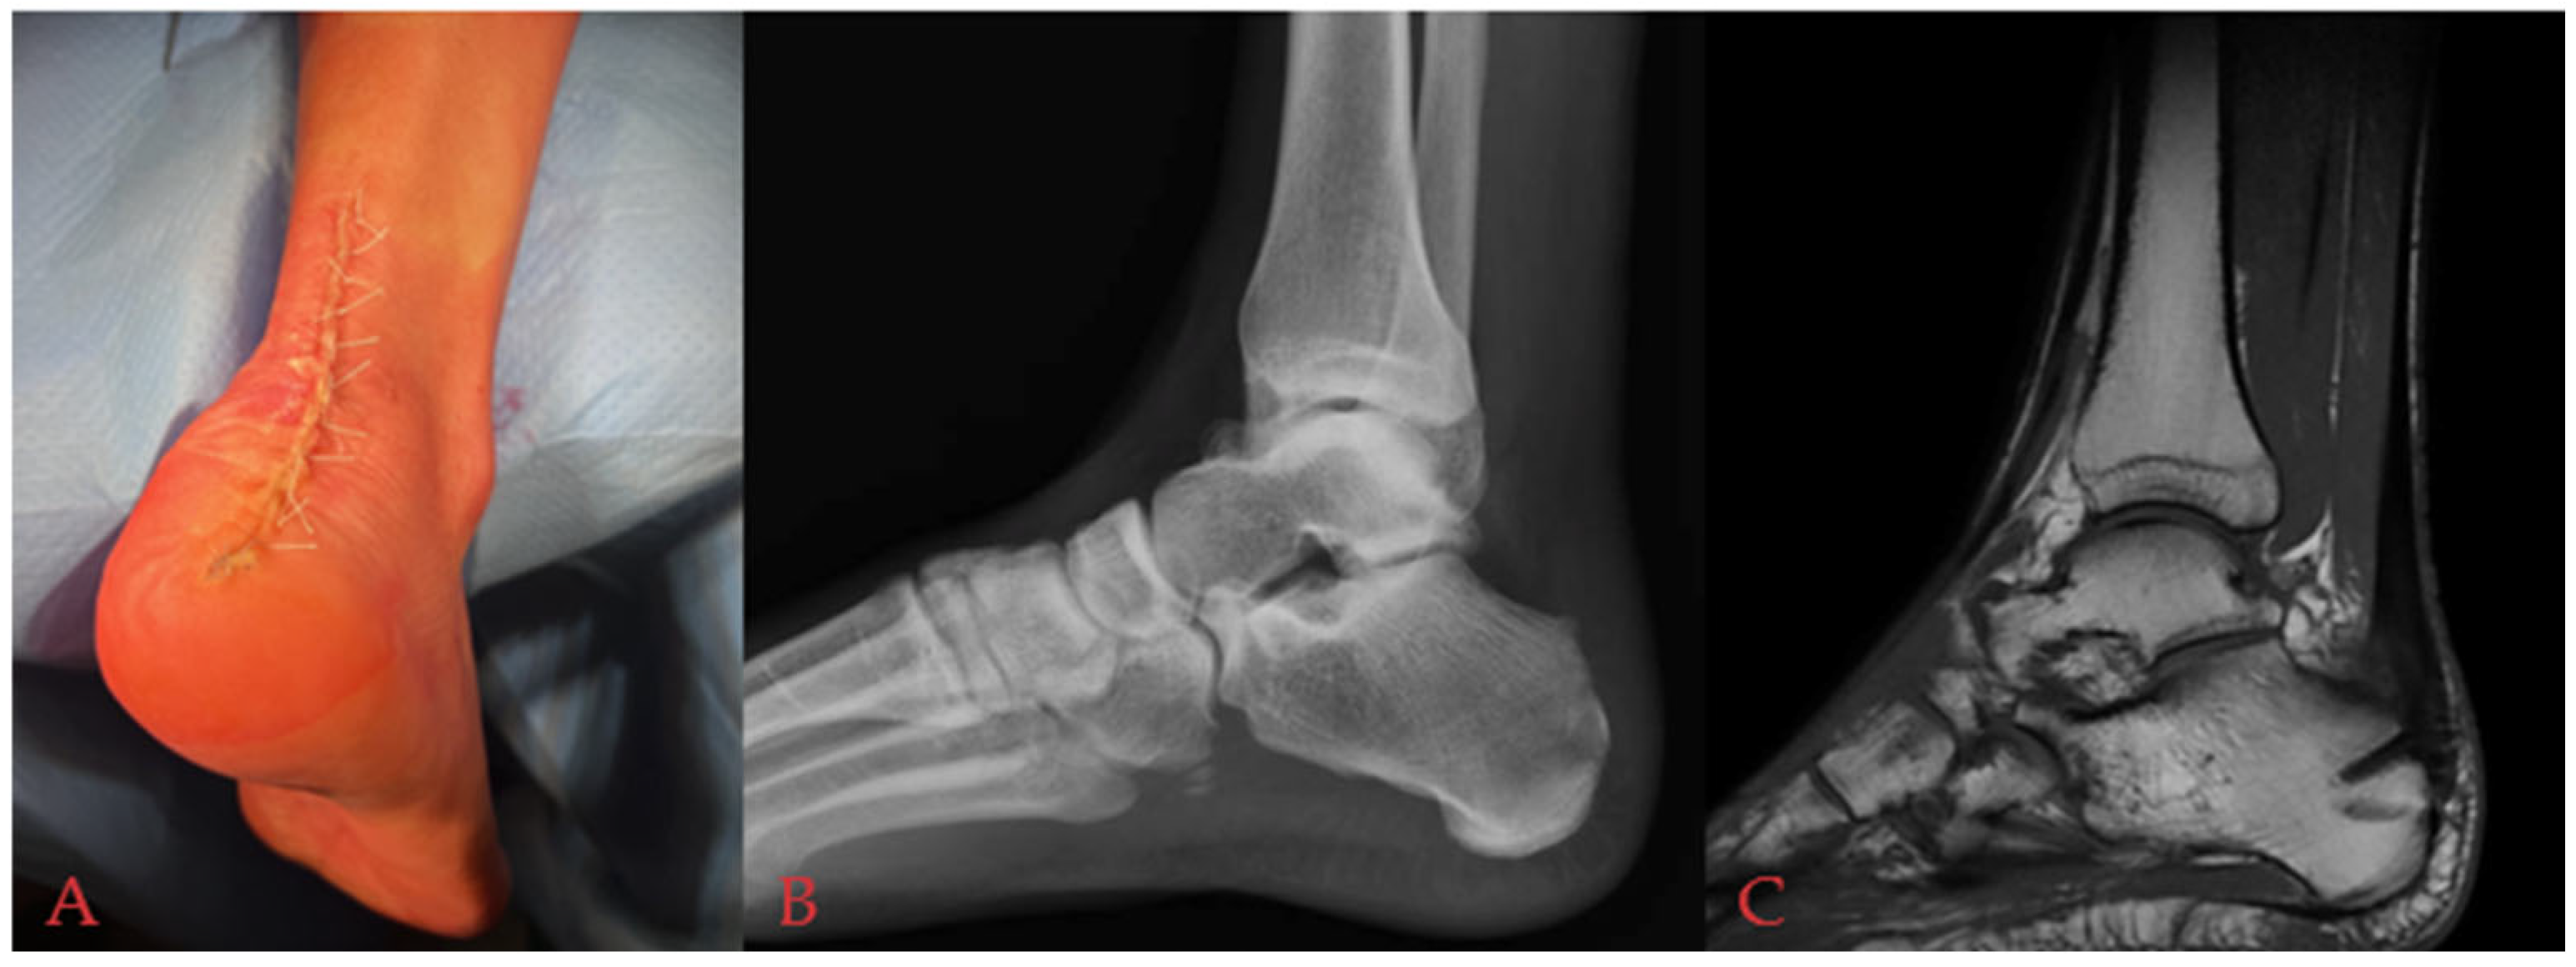

Successful Achilles Tendon Reattachment Using SpeedBridge in Haglund’s Triad Patients